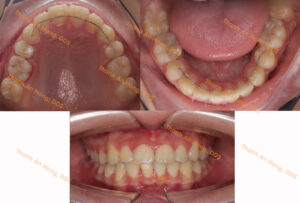

HÌNH ẢNH THỰC TẾ

Sắp đều răng trong độ tuổi tăng trưởng với mắc cài